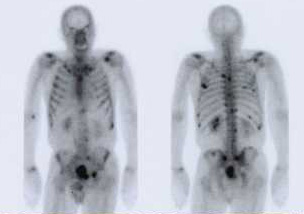

Knochenszintigramm: Mann mit Knochenmetastasen